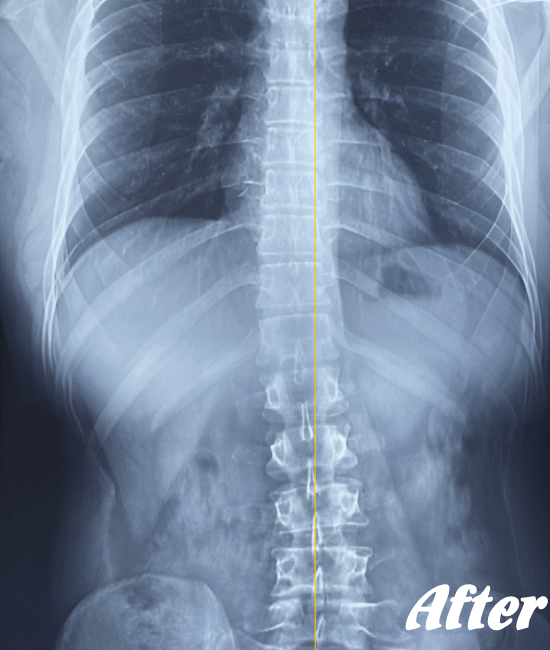

病院では、側弯の程度はレントゲンによる画像検査で弯曲の程度を調べます。

Cobb角(コブ角)とは、背骨の曲がり具合の角度を表す用語ですが、コブ角が10~25度程度なら経過観察。コブ角が25°~40°程度ならコルセットなどの装具を装着する療法、コブ角が40°~50°以上であれば手術…といった目安になります。

先天性や弯曲角度が大きい突発性側弯症は適応外になりますが、普段の姿勢の悪さに起因する機能性側弯症や初~中期の突発性側弯症であれば、施術対象になります。

ただし、弯曲が20°以上になると改善が難しくなってきます。また、脊柱(背骨)が側屈しているだけなら良いのですが、椎骨が回旋してしまっている場合の改善は、肋骨の変形もともなうため改善が難しくなります。